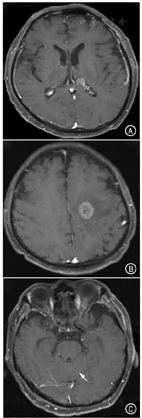

患者男,62岁,头晕、头痛、颈部不适1个月于2017年6月27日来我院就诊。既往无慢性病史。约5年前,患者行左股肿物(约6 cm × 3 cm)切除术。术后病理:软组织肉瘤,黏液型纤维肉瘤(G2),分期:T2bN0M0,ⅡB期(图1)。免疫组化:actin(-),desmin(-),S-100(+/?),Ki-67(+),CD34(+),bcl-2(+),细胞角蛋白(-),Vim(+),神经元特异性烯醇化酶(+)。术后1年余肿瘤复发,行局部肿瘤根治性扩大切除术。术后患者行局部放射治疗(60 Gy/30次),同步阿霉素+异环磷酰胺联合化疗。入院查体:锥体束征(-),颅神经(-),项强征(+)。左股近端内侧见长约20 cm手术疤痕,局部未触及肿物。卡氏评分80分,格拉斯哥评分14分。肝肾功能、血常规和凝血检查正常,乙型和丙型肝炎病毒、梅毒、艾滋病检测阴性。头部磁共振检查示,左侧侧脑室内及左侧放射冠多发类圆形占位病变,病灶明显强化,符合脑转移瘤特点;脑沟回内弥漫线样强化,以小脑沟回内为著(图2)。颈、胸和腹部CT未见占位病变。腰穿:颅压220 mmH2O,蛋白0.32 g/L,糖3.10 mmol/L,氯126.4 mmol/L,潘式反应(-),白细胞10×106/L,无红细胞。脑脊液病毒、细菌和结核菌检查均为阴性。脑脊液细胞学检查(液基细胞制片联合巴氏染色)找到肿瘤细胞(图3)。诊断为脑膜转移。行鞘内化疗及全脑放疗的综合治疗。鞘内化疗阿糖胞苷50 mg+地塞米松5 mg,每周1次。同步给予全脑放疗,采用RapidArc容积调强放疗技术,6 MV X射线,40 Gy/20次,4周完成。治疗2周后,头晕、后颈部疼痛症状明显缓解。治疗过程中,患者出现双下肢一过性麻木等腰骶部脊神经神经根刺激症状,给予对症治疗后缓解。20次全脑放疗并5次鞘内化疗后,头晕、头疼和后颈部疼痛症状基本消失,KPS评分100分。脑脊液脱落细胞学检查:找到少量肿瘤细胞。复查头部MRI较前无明显变化,颈、胸和腹部CT未见肿瘤病灶。自脑膜转移诊断至今4月余,患者无症状生存。

黏液型纤维肉瘤脑转移非常罕见,既往仅有少量报道[2,3,4]。脑脊液细胞学检查是明确脑膜转移诊断的金标准。本例患者脑脊液中找到的肿瘤细胞具有典型恶性特征,细胞体积大,核质明显增大,似裸核,染色质粗颗粒样,可见多核。影像学检查显示多发柔脑膜强化,为本病特征性影像学表现。另外,可见转移病灶位于脑室内,为脑膜转移提示性影像学表现。本例患者脑膜转移发生的原因,可能为肿瘤细胞血行转移所致,也可能为脑室内转移病灶肿瘤细胞脱落进入脑脊液中增殖所致[5]。本例患者既往存在纤维肉瘤病史,脑膜转移治疗前及治疗后全身检查均未见其他新发肿瘤病灶。